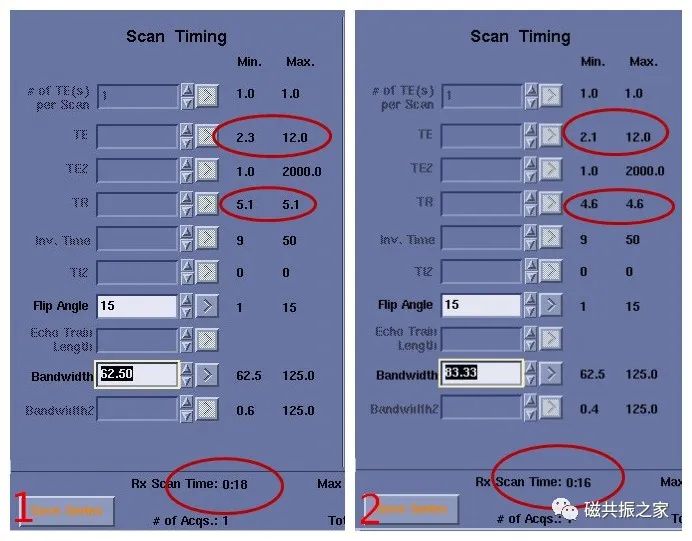

三、缩短TE或TR

磁共振一个序列的采集时间跟TR的长短密不可分,如FRFSE使用一个恢复脉冲使TR时间明显缩短,则扫描时间比FSE序列更快了。GRE序列的成像时间比SE序列快得多就是因为GRE的TR比SE的TR短得太多。在GRE序列中TE与TR是相互影响的,如缩短TE或TR值则可加快扫描速度。

很多序列使用的是系统的极限参数,也就是系统允许的最短TE与TR值。当改变某一些参数时会导致TE的延长,TE的延长则会导致TR的延长,最终导致扫描时间的增加。改变最短TE或TR值,则会缩短扫描时间。